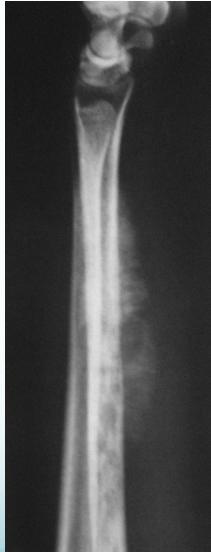

Radiological Features

- X-ray:

- Diaphyseal

- Bone destruction

- New bone formation:

- Along the bone

- “Onion-peel” layers

- ? “Sun-ray”

- ? Codman’s triangle

- Secondaries – in skeleton

Source: Apley’s System of Orthop. And Fractures